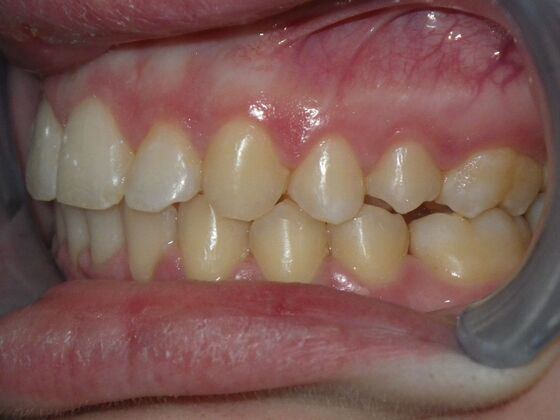

Orthodontics: Case 4

Description

Patient presents with constricted upper and lower arches, numerous crossbites on right side, with upright central incisors on upper arch that will need to be flaired to provide adequate lip support. I decided to use on this case self ligating brackets, to help with expansion purposes. This case turned out very well with flairing of upper centrals, crossbite corrections, expansion of arches, as well as establishing better arch form and symmetry.